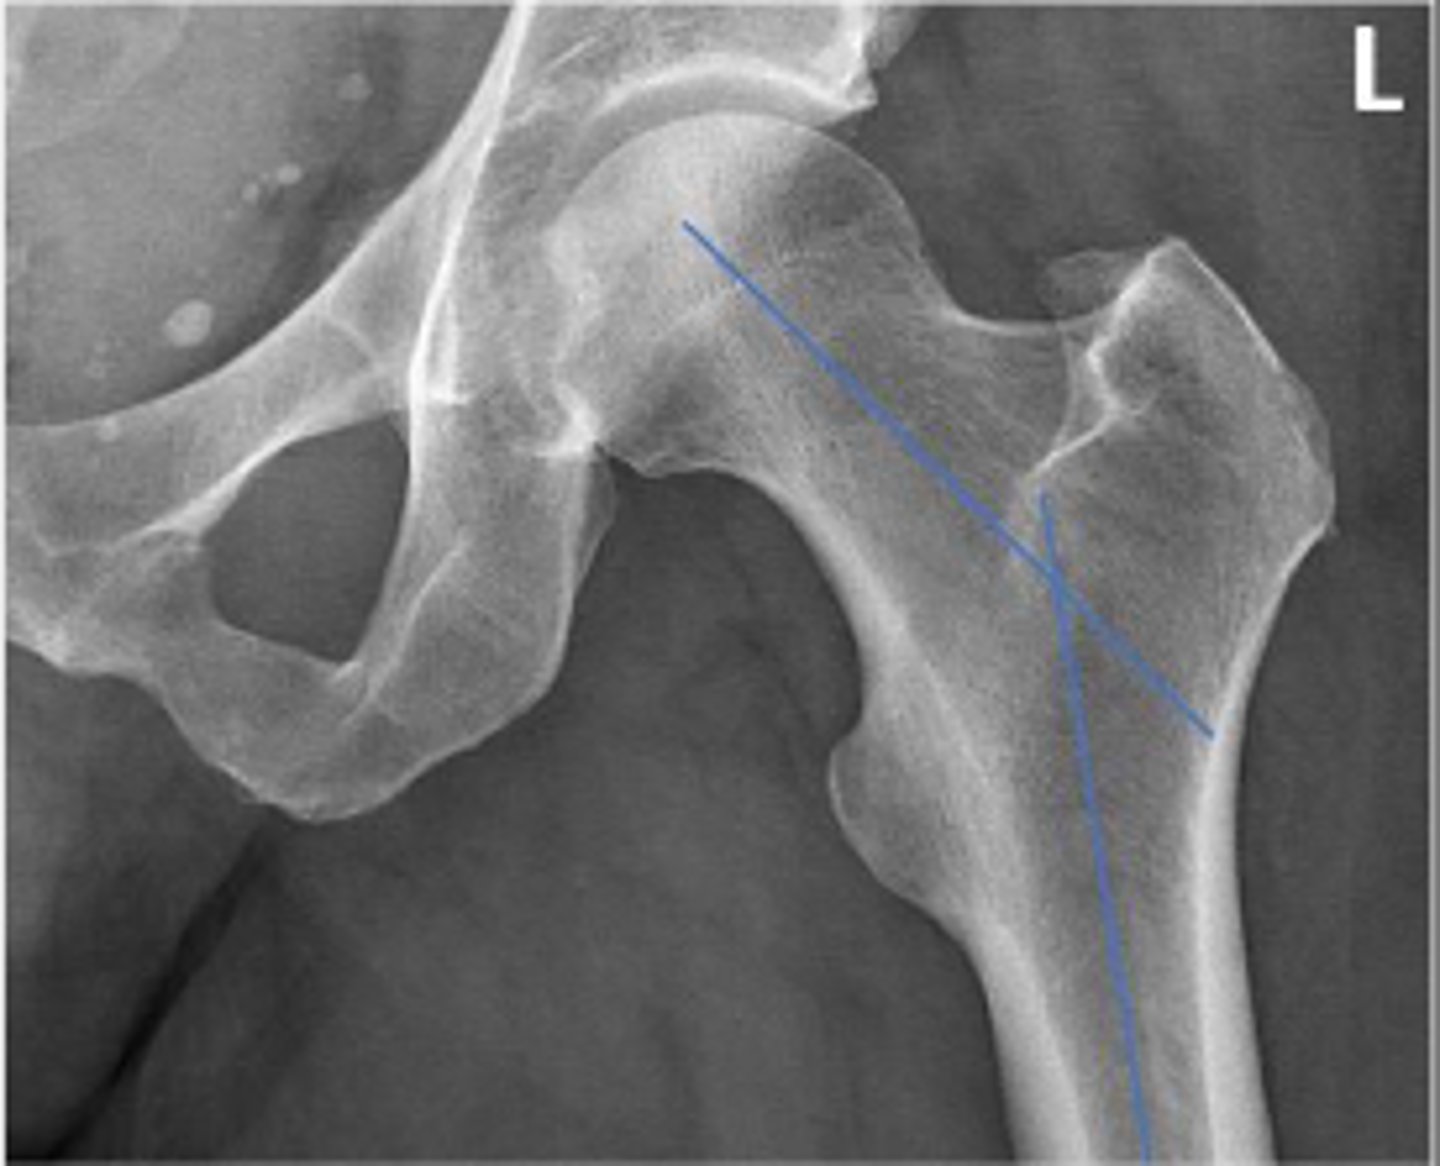

Femoral angle

What is the name of the assessment?

120-130 degrees

What is the normal range for this assessment?